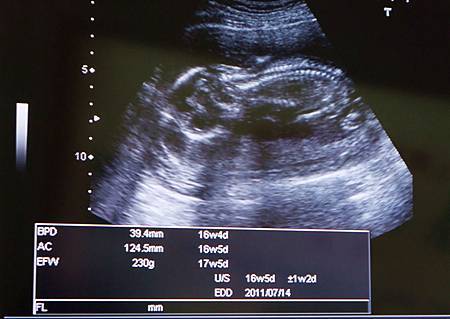

羊膜穿刺想像的恐懼不少,實際做了後發現腹部扎針沒有太多痛覺,類似一般的打針,也或者我已先把肚子扎針想得很痛很痛,乃至於對照之下,針一紮下去,就鬆了一口氣,也謝謝寶寶和我一樣乖,完全不動地讓醫生完成羊膜穿刺。術後稍坐一會,並不覺得有啥異樣,散步到診所附近咖啡館坐了一會聊了天,吃了一塊蛋糕,後來回家沒躺床,一切如常,等著收檢驗報告。